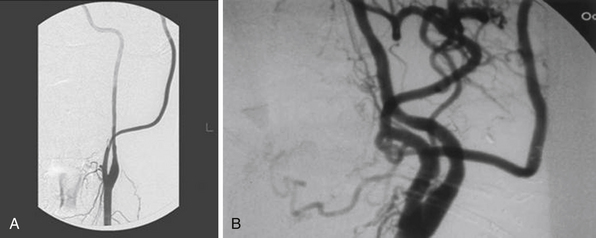

A bur hole is made and enlarged to the size of a very small craniotomy (~ 2-2.5 cm) under the microscope (Figs. 18.9 and 18.10), and the recipient vessel is exposed in the distal sylvian fissure over a length of 1 cm. A rubber dam is applied and the anastomosis is performed with a 9-0 nylon suture in a running fashion. The back wall is anastomosed first, followed by the front wall. Temporary clips are applied on the M4 recipient vessel during the anastomosis. Postoperatively, the patients are followed up with angiography (Fig. 18.11) or CT angiography (Fig. 18.12).18

It is important to recognize that during intraoperative angiography the graft may only supply a single division of the recipient territory (i.e., a single M2 division). This should not be a concerning sign. In general, this is due to the fact that there is significant competitive flow coming through the anterior communicating artery from the contralateral side, which is protective, and the surgeon ought not to change the strategy during the case (Fig. 18.23).